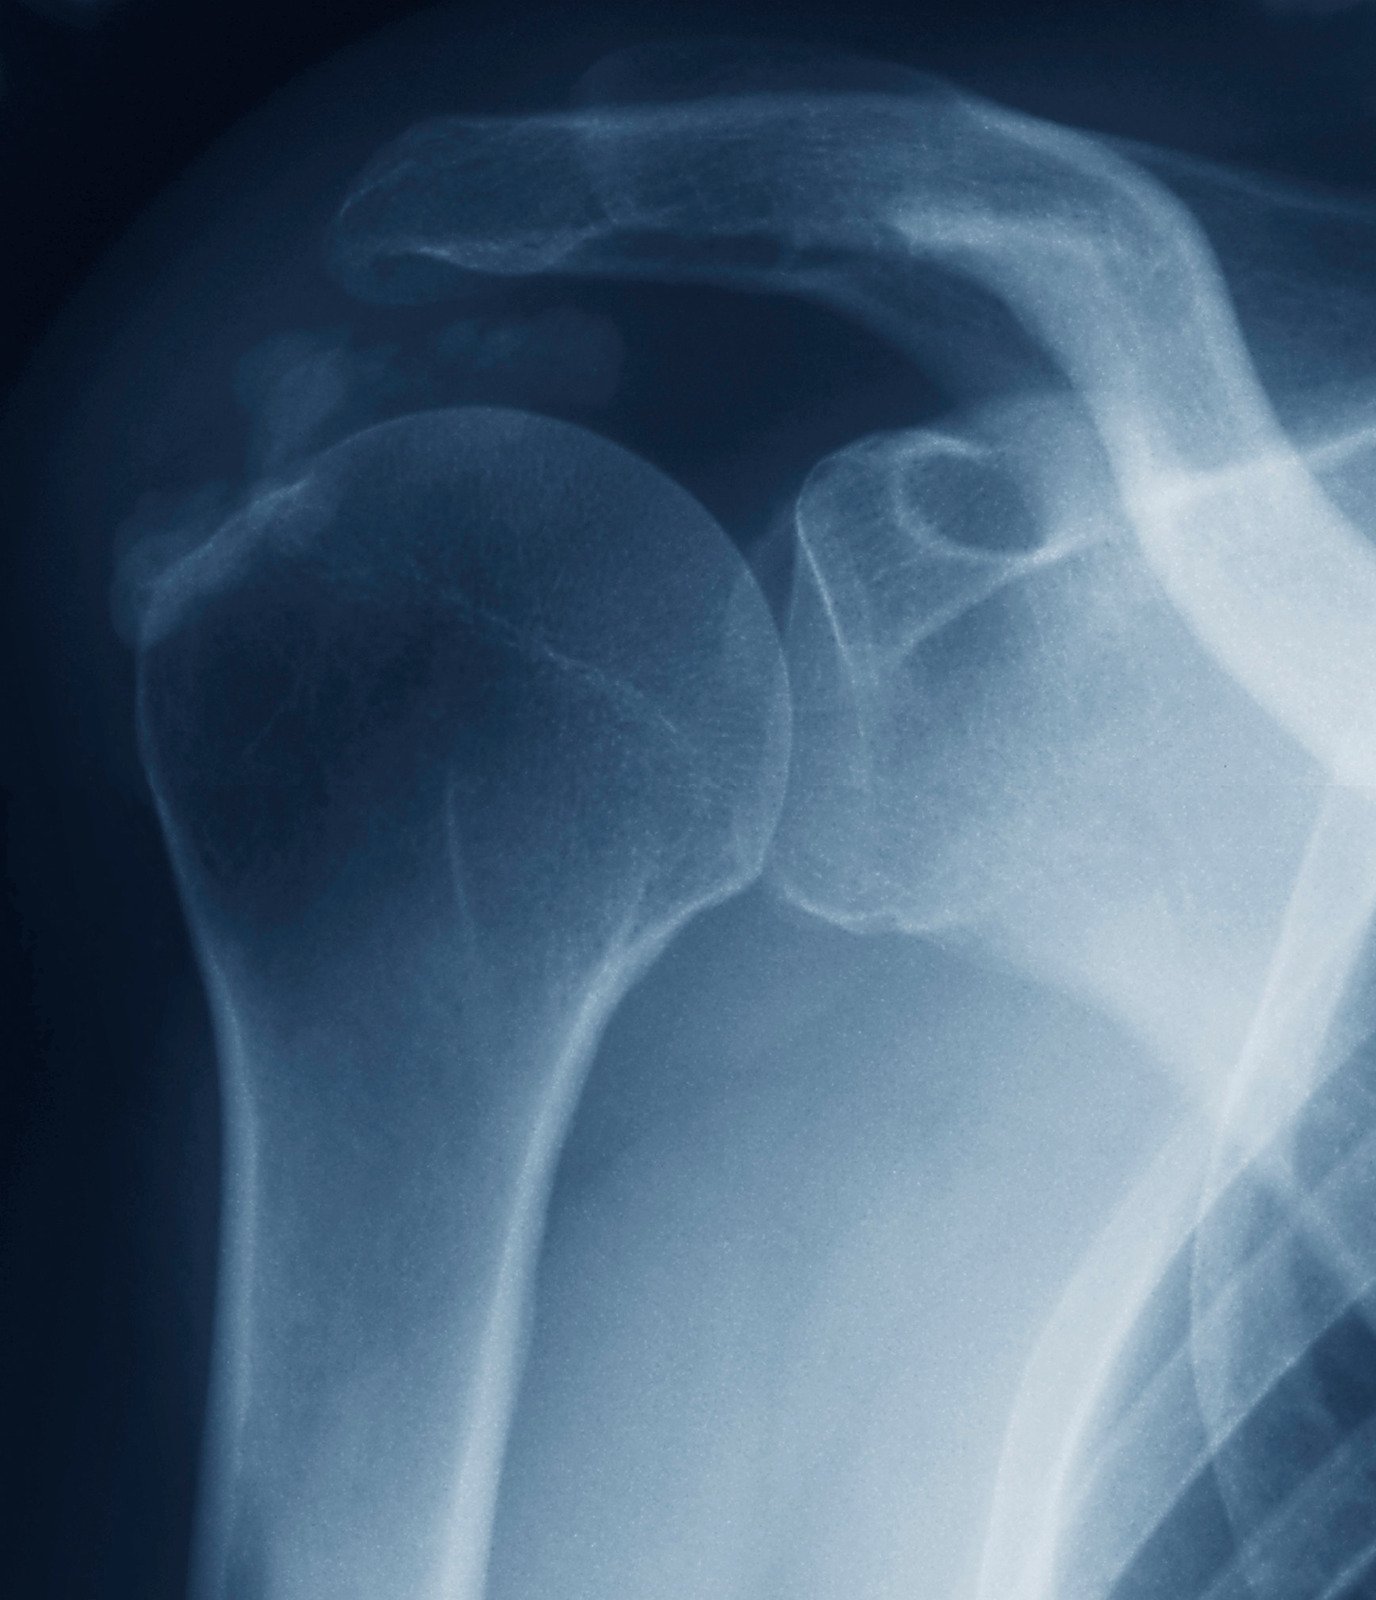

X-ray 검사 → 어깨 힘줄 부위에 흰색 석회 확인 가능

👉 단순 어깨 통증이 아닌 갑작스러운 극심한 통증 + X-ray에서 석회 확인이 특징입니다.

석회화건염 → 갑작스럽게 극심한 통증 발생, X-ray에 석회 보임